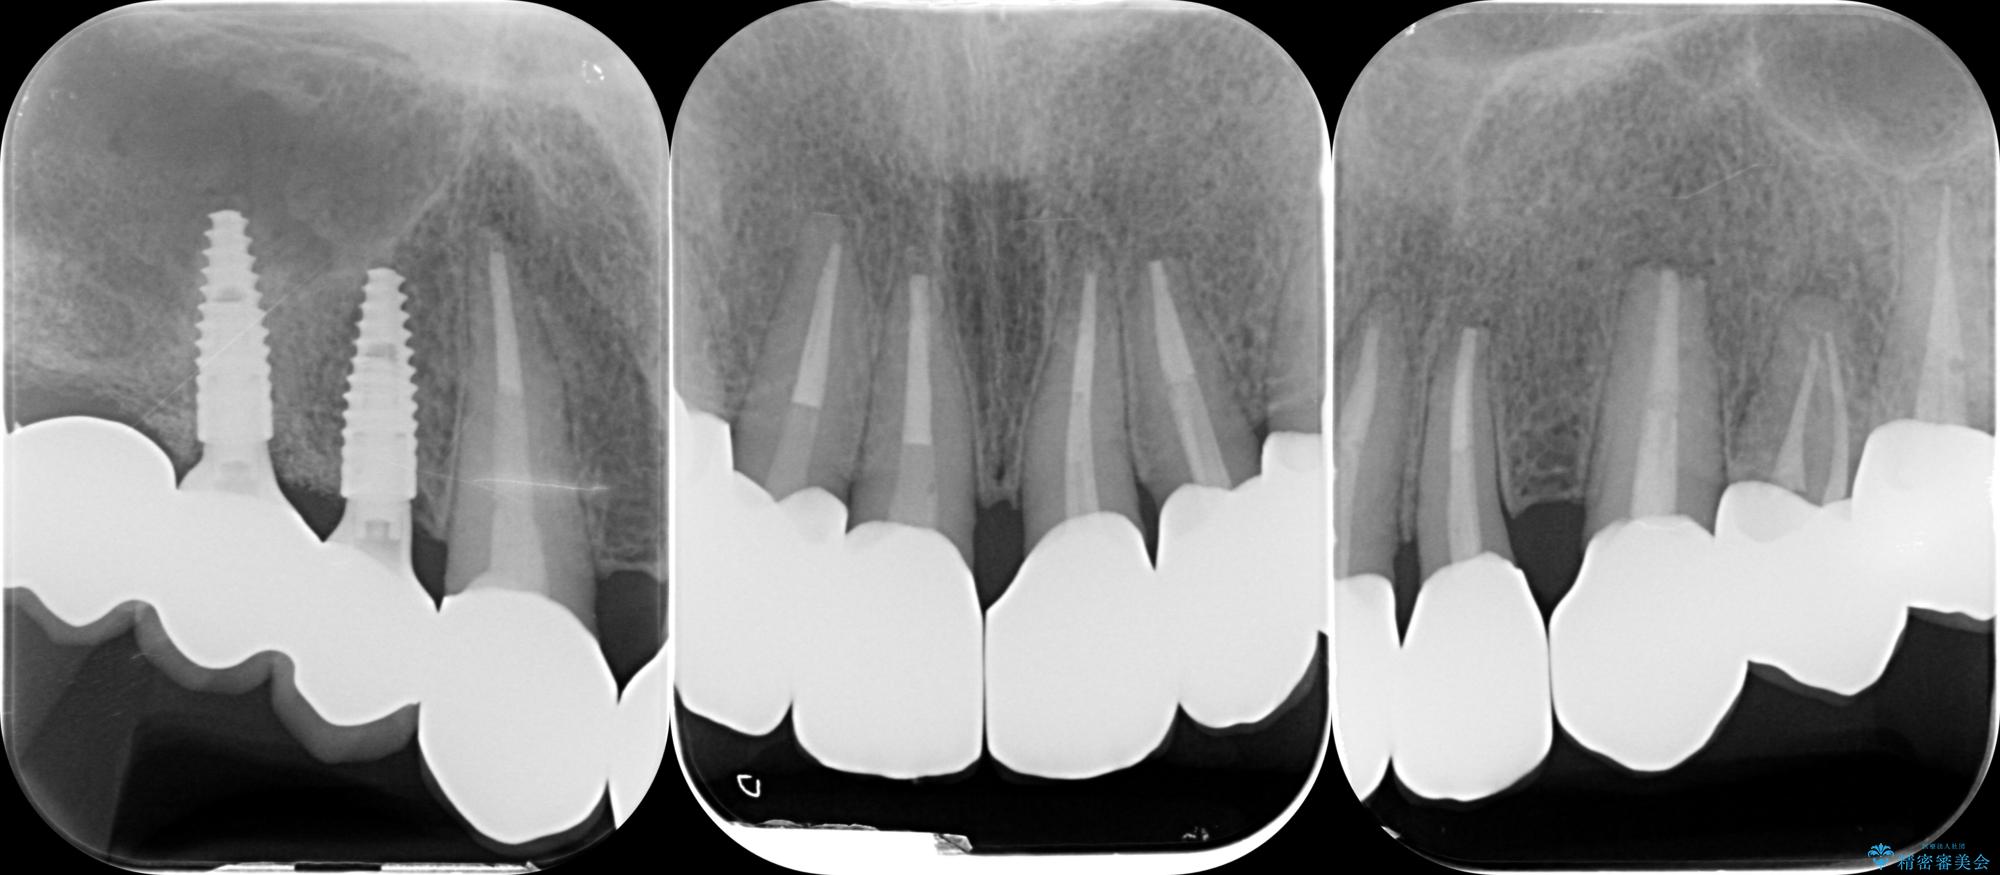

歯周組織検査を行うと歯ぐきからは容易に出血し、X線検査より歯とセラミッククラウンの適合が悪い(ピッタリと合っていない)状態が示唆され、歯ぐきの炎症を惹起している状態でした。

セラミッククラウンを除去し仮歯を装着し、歯周外科手術を行い歯ぐきの状態を改善したのち、適合の良いセラミッククラウンを再作製をする治療計画としました。

- 90.2万円(ジルコニアクラウン×6・仮歯×6 ・歯周外科手術)費用は治療当時の料金となります